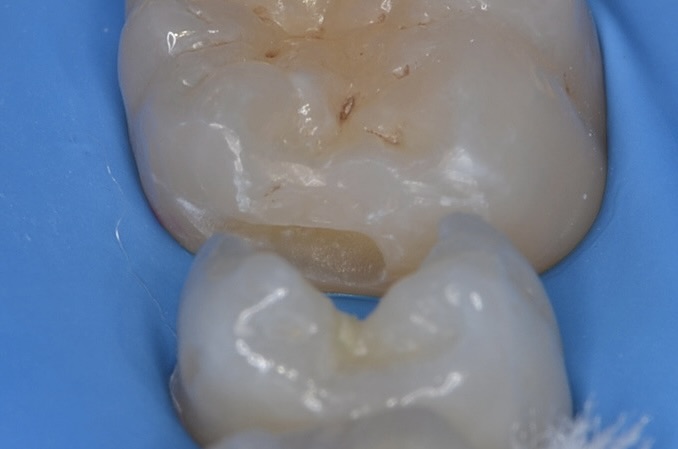

ダイレクトボンディング

滑らかな曲線になるようにレジンで埋めます。 -

天然歯の自然な形態を模倣してレジンを充填しました。 -